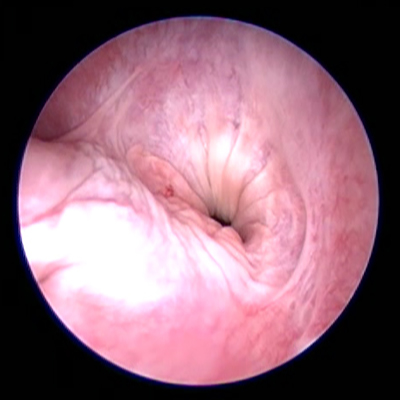

Diagnostiek

Het stellen van een diagnose kan soms net spoorzoeken zijn. Soms is het eenvoudig en soms is het lastig.

Onze diagnostische mogelijkheden hebben we uitgebreid door de aanschaf van vele soorten van apparatuur en het volgen van allerlei cursussen.